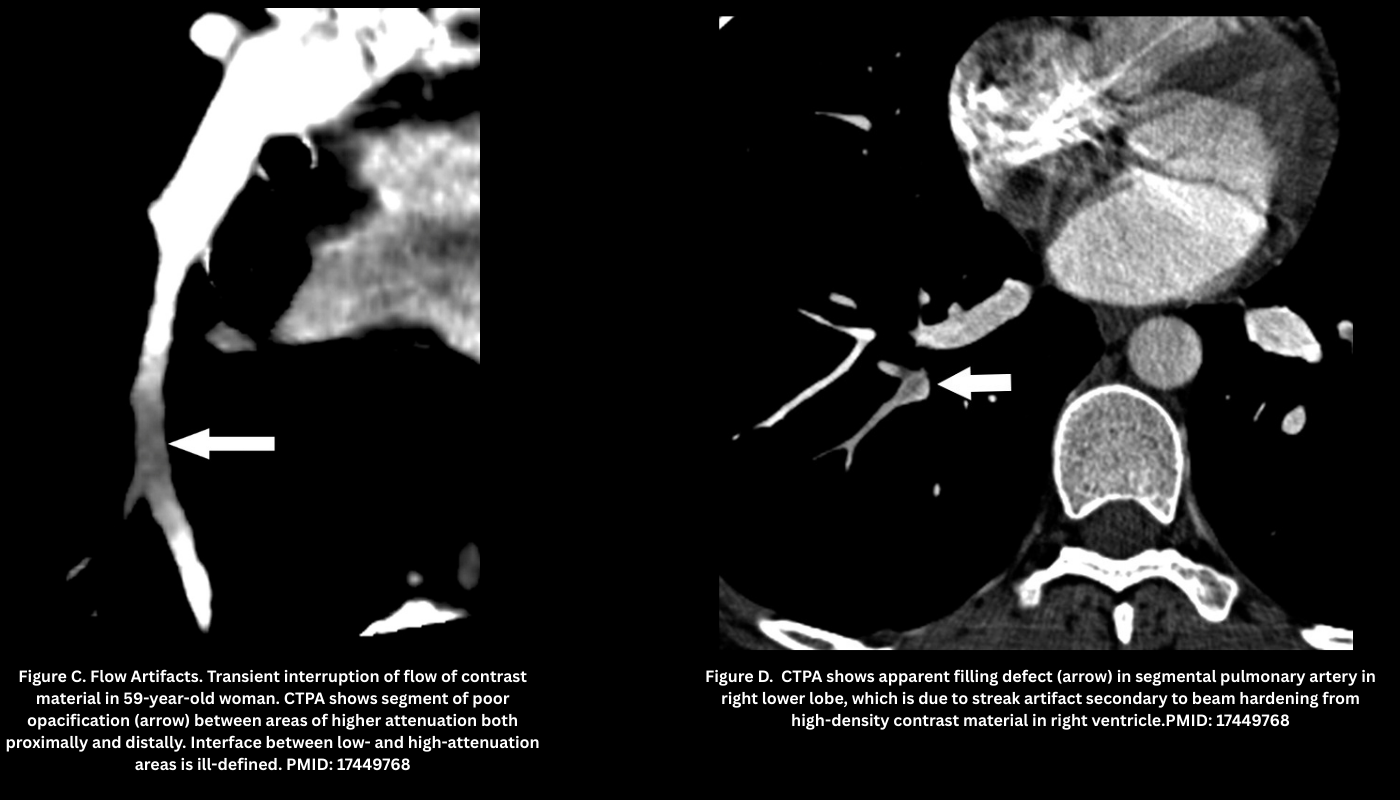

- Flow-related artifact (transient interruption of contrast). Figure C.

- Poor mixing of contrast/unopacified blood → patchy low attenuation in lower lobe arteries.

- Appearance: Filling defect with poorly-defined margins from mixing of opacified and unopacified blood (“transient interruption of contrast”), attenuation >78 HU.

- Beam-Hardening Artifact (Figure D)

- Appearance: Dense streaks from high-density structures (e.g., pooled contrast agent in the right atrium, SVC or other adjacent vessels, metallic structures such as pacemakers, or the patient’s arms if they cannot be elevated above the chest), often projecting over the right pulmonary artery or medial upper lobe vessels.

- Pearl: Use a saline chaser and optimized bolus protocols to reduce SVC streaking.